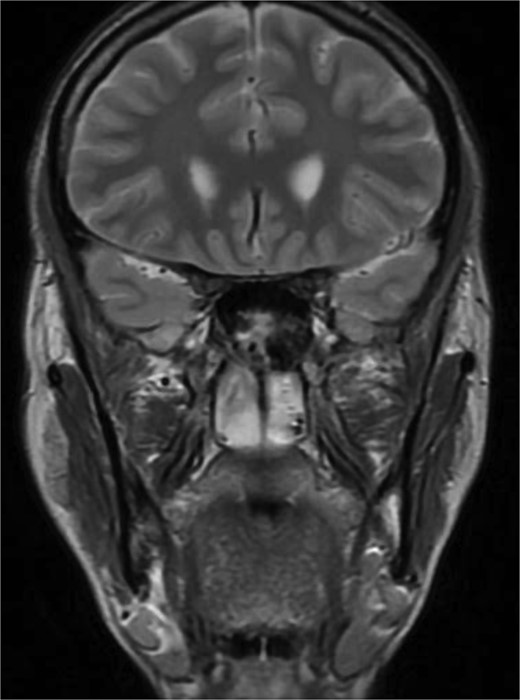

MRI of paranasal sinuses shows the sphenoid sinus is expanded and bulging superiorly into the pituitary fossa causing displacement of pituitary gland and stalk without mass effect upon the optic chiasm. It extends laterally causing effacement of the cavernous sinus.

Patient presented to the emergency department with four days history of sever left side headache associated with nausea and vomiting, and nasal discharge with on\off nasal obstruction. Two days history of diplopia with lateral gaze of the left eye, with decrease the visual acuity. Ophthalmologic examination revealed left abducens nerve palsy. Other neurologic examinations were within normal. Endoscopic nasal examination revealed left multiple grade two nasal polyps occupying the middle meatus. Pre-operative brain computed tomography (CT) shows bilateral near total opacification and expansion of the paranasal sinuses and nasal cavity (Fig. 1). Additionally, there is evidence of invasion of the left cavernous sinus with encasement of cavernous segment of left internal carotid artery (ICA). Furthermore, pituitary gland and optic chiasm displaced superiorly. Magnetic resonance imaging revealed that the sphenoid sinus is expanded and bulging superiorly into the pituitary fossa causing displacement of pituitary gland and stalk without mass effect upon the optic chiasm (Fig. 2). It extends laterally causing effacement of the cavernous sinus and left Meckel’s cave. No evidence of intracranial extension. The patient underwent functional endoscopic sinus surgery with computer-assisted navigation system. Intraoperatively, sphenoid sinus was full of fungal mud and mucin (Fig. 3). The polyps were removed completely from the nasal cavities, fungal mud, and mucin were removed from the sinuses (Figs 4 and 5). Patient had dramatic improvement after surgery, the rhinosinusitis symptoms are resolved, the diplopia has been improved, and the paranasal sinuses were clear. The patient was discharged with topical corticosteroid and saline irrigations.